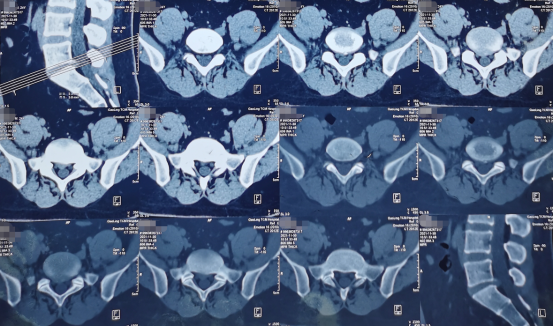

术前影像学资料